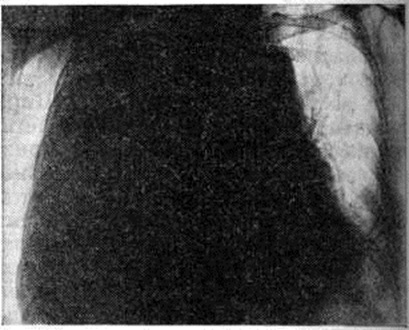

Рис. 4.

Прямая рентгенограмма грудной клетки больного с массивным (тотальным) плевритом: выпот, заполняющий правую плевральную полость, затемняет все правое легочное поле и оттесняет органы средостения влево.